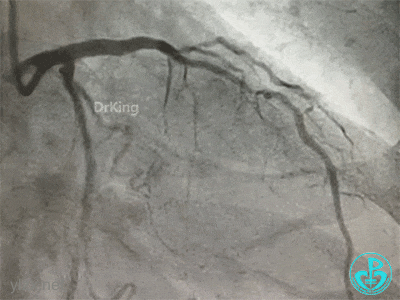

冠脉造影

右冠脉近中段不规则狭窄。短左主干中度狭窄,前降支开口严重狭窄,多功能造影导管推注造影剂时无反流,导管退出左主干开口造影发现左主干狭窄严重。

更换指引导管,导丝分别进入前降支和回旋支,球囊分别扩张前降支开口和回旋支开口,IVUS确认左主干及分支开口病变,前降支中段植入支架,对角支开口球囊扩张。

左主干分叉病变采取Crush双支架术式,回旋支开口植入支架,前降支开口球囊挤压后左主干到前降支植入支架(Crush双支架术式)。